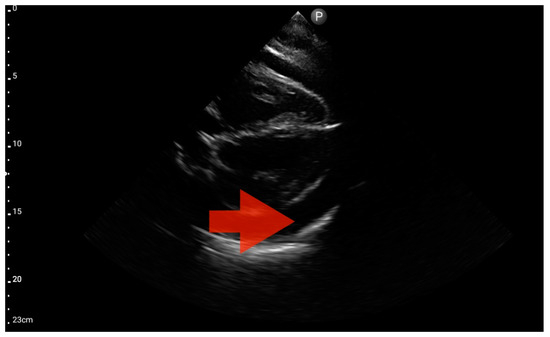

Pericardial effusion; position: apical four-chamber (FATE protocol). Sector probe; the red arrow indicates free fluid in the pericardium, which did not cause a sonographic image of cardiac tamponade (source: author’s material—DK).

In our study, the FATE protocol was also followed by the assessment of the inferior vena cava (IVC) diameter. IVC dilation was observed in three patients (Figure 15). We did not find this parameter useful in our pre-hospital setting. Furthermore, such assessment is relatively challenging and not always possible to perform quickly. In four of the analyzed patients, IVC assessment was not possible. As a result, in our group, the sensitivity and specificity for the IVC assessment were 0.29 (95%CI: 0.04–0.71) and 0.8 (95%CI: 0.28–1.0), respectively. The positive predictive value was 0.67 (95%CI: 0.09–0.99), and diagnostic accuracy was 0.5 (95%CI: 0.21–0.79).

Figure 15.

Inferior vena cava (IVC) dilation. Sector probe; the red arrow marks the inferior vena cava; the width is not dependent on the phase of the patient’s breath and shows significant dilatation (source: author’s material—DK).